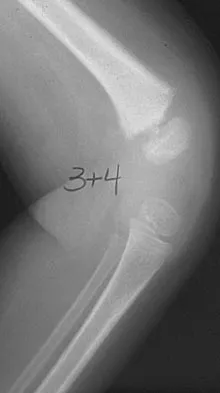

A 78-year-old woman falls onto her nondominant left elbow and sustains the injury shown in Figure 5. What treatment option allows her the shortest recovery time and highest likelihood of good function and range of motion?

Explanation

Total elbow arthroplasty has become the treatment of choice for complex, comminuted distal humeral fractures in patients older than age 70 years. It yields a faster recovery with more predictable functional outcomes, although limitations of lifting weight of more than 5 pounds must be followed to avoid loosening. Kamineni S, Morrey BF: Distal humeral fractures treated with noncustom total elbow replacement. J Bone Joint Surg Am 2004;86:940-947.